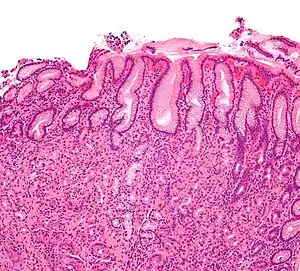

Entretanto, 40% dos casos de gastrite crônica nada mostram. Por isso, considera-se que o diagnóstico das gastrites crônicas é, fundamentalmente, histológico, ou seja, pelo exame microscópico de fragmentos da mucosa colhidos por pinça de biópsia que passa através do próprio endoscópio.